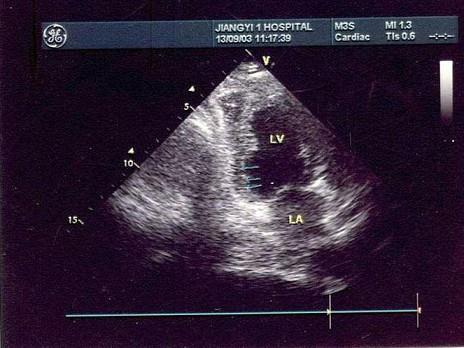

患者有心梗史,如图所示最可能诊断是?(?)A.室壁瘤形成B.室间隔呈反"S"型C.扩张型心肌病  D.真性室壁瘤E.限制性心肌病

问题 患者有心梗史,如图所示最可能诊断是?(?)

选项 A.室壁瘤形成 B.室间隔呈反"S"型 C.扩张型心肌病   D.真性室壁瘤 E.限制性心肌病

答案 A